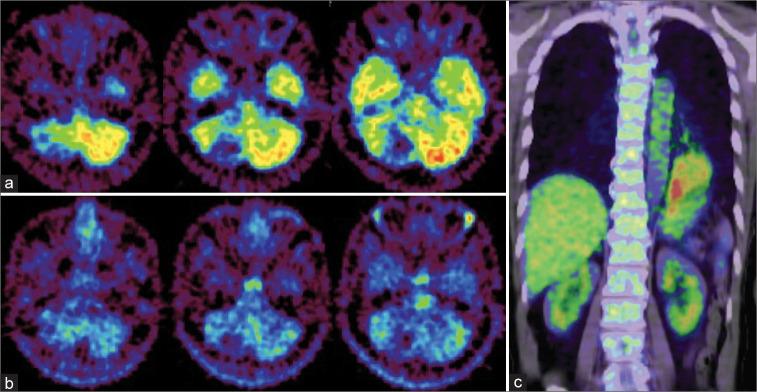

We report an unusual case of metastatic brain tumors without accumulation of FDG or MET, contrasting with high FDG uptake in the primary lung lesion. The brain lesions were identified as adenocarcinoma with a more mucus-rich background, contributing to the indistinct accumulation of both FDG and MET.

我们报告了一例不寻常的转移性脑肿瘤病例,FDG和MET均无积聚,而原发性肺病变中FDG摄取较高。脑病变被鉴定为腺癌,背景黏液较多,导致FDG和MET的积聚不明显。